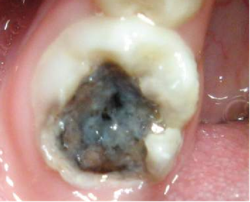

第4阶段:感染牙髓,“痛到失眠”。

表现:自发剧痛(尤其是晚上),牙龈可能肿胀。

原因:细菌侵入牙髓(牙神经),引发炎症和感染。

第5阶段:烂到牙根,牙齿“报废”。

表现:牙齿碎裂、牙根脓肿,咬合剧痛,脸部肿胀。

原因:牙根和周围骨质被破坏,形成脓包。